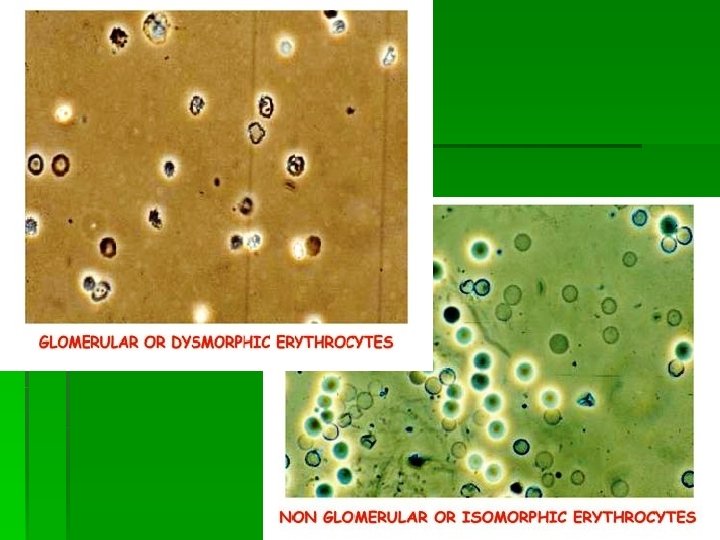

Гематурия – более 1000 эритроцитов в 1 мл мочи Гематурия как результат паренхиматозного заболевания почек § § § Продолжительная Безболезненная Микрогематурия (иногда макрогематурия) Двухсторонняя Эритроцитарные цилиндры в моче, дисморфные Эр Гематурия при заболевании мочевыводящих путей § Интермиттирующая § Связана с болью в области почек § Макрогематурия § Односторонняя § Изоморфные эритроциты